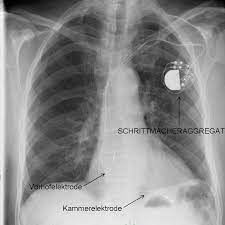

Implantationen Umm Universitatsmedizin Mannheim

Implantationen Umm Universitatsmedizin Mannheim from www.umm.de